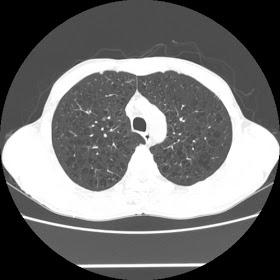

A 52 Years old man suffering with chest pain since 3 years

HRCT Chest